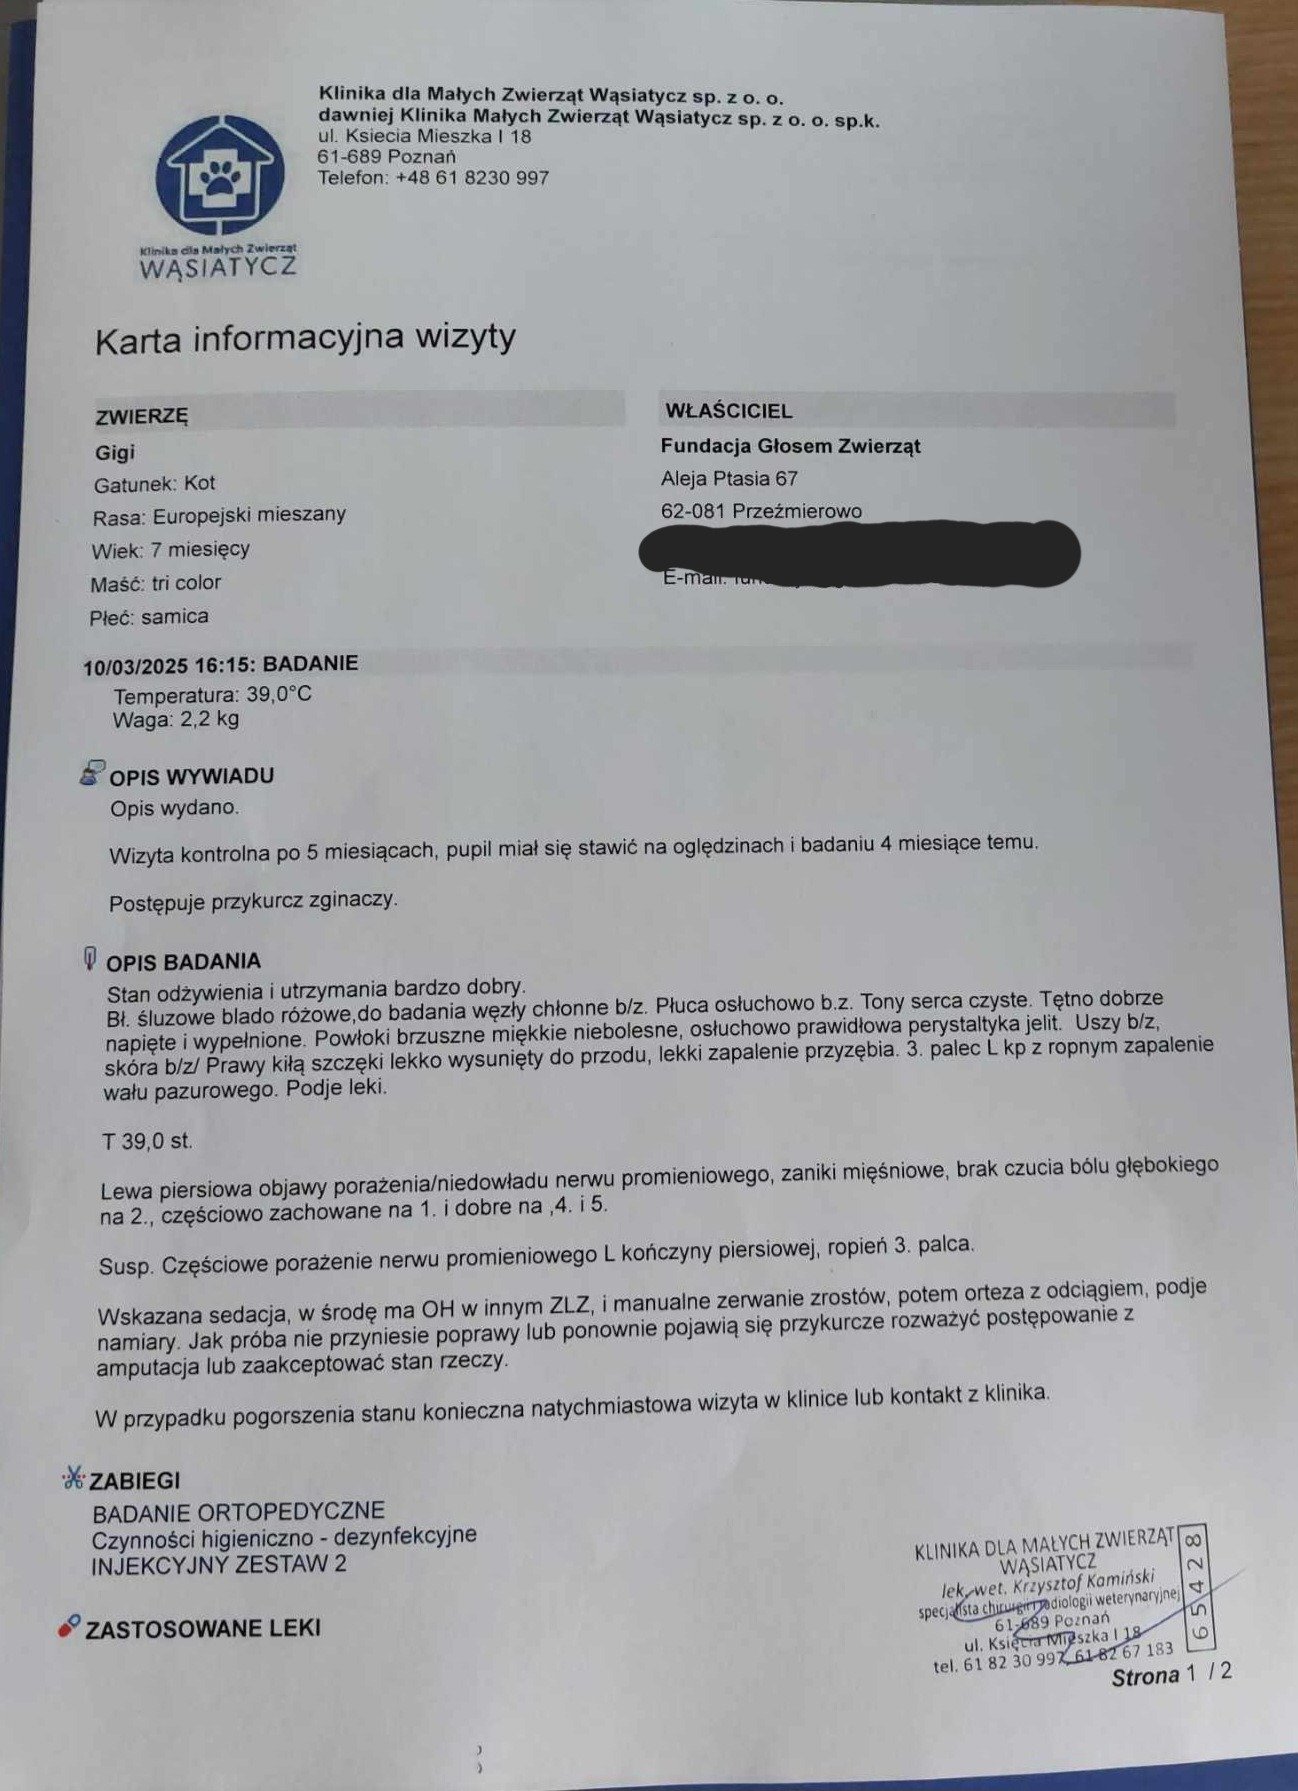

Gigi trafiła do nas jako kilkumiesięczny kotek, z wykrzywioną łapką.

Dotychczasowa rehabilitacja nie przyniosła oczekiwanego skutku, łapka wymaga manualnego zerwania zrostów, wyprostowania jej i założenia usztywniacza w postaci ortezy.

Aby taką ortezę wykonać należało kotka poddać sedacji, zrobić odlew łapy i poczekać kilka tygodni na wykonanie gotowej ortezy, robionej indywidualnie dla Gigi.

(zdj.piniżej - Gigi podczas robienia odlewu łapy)